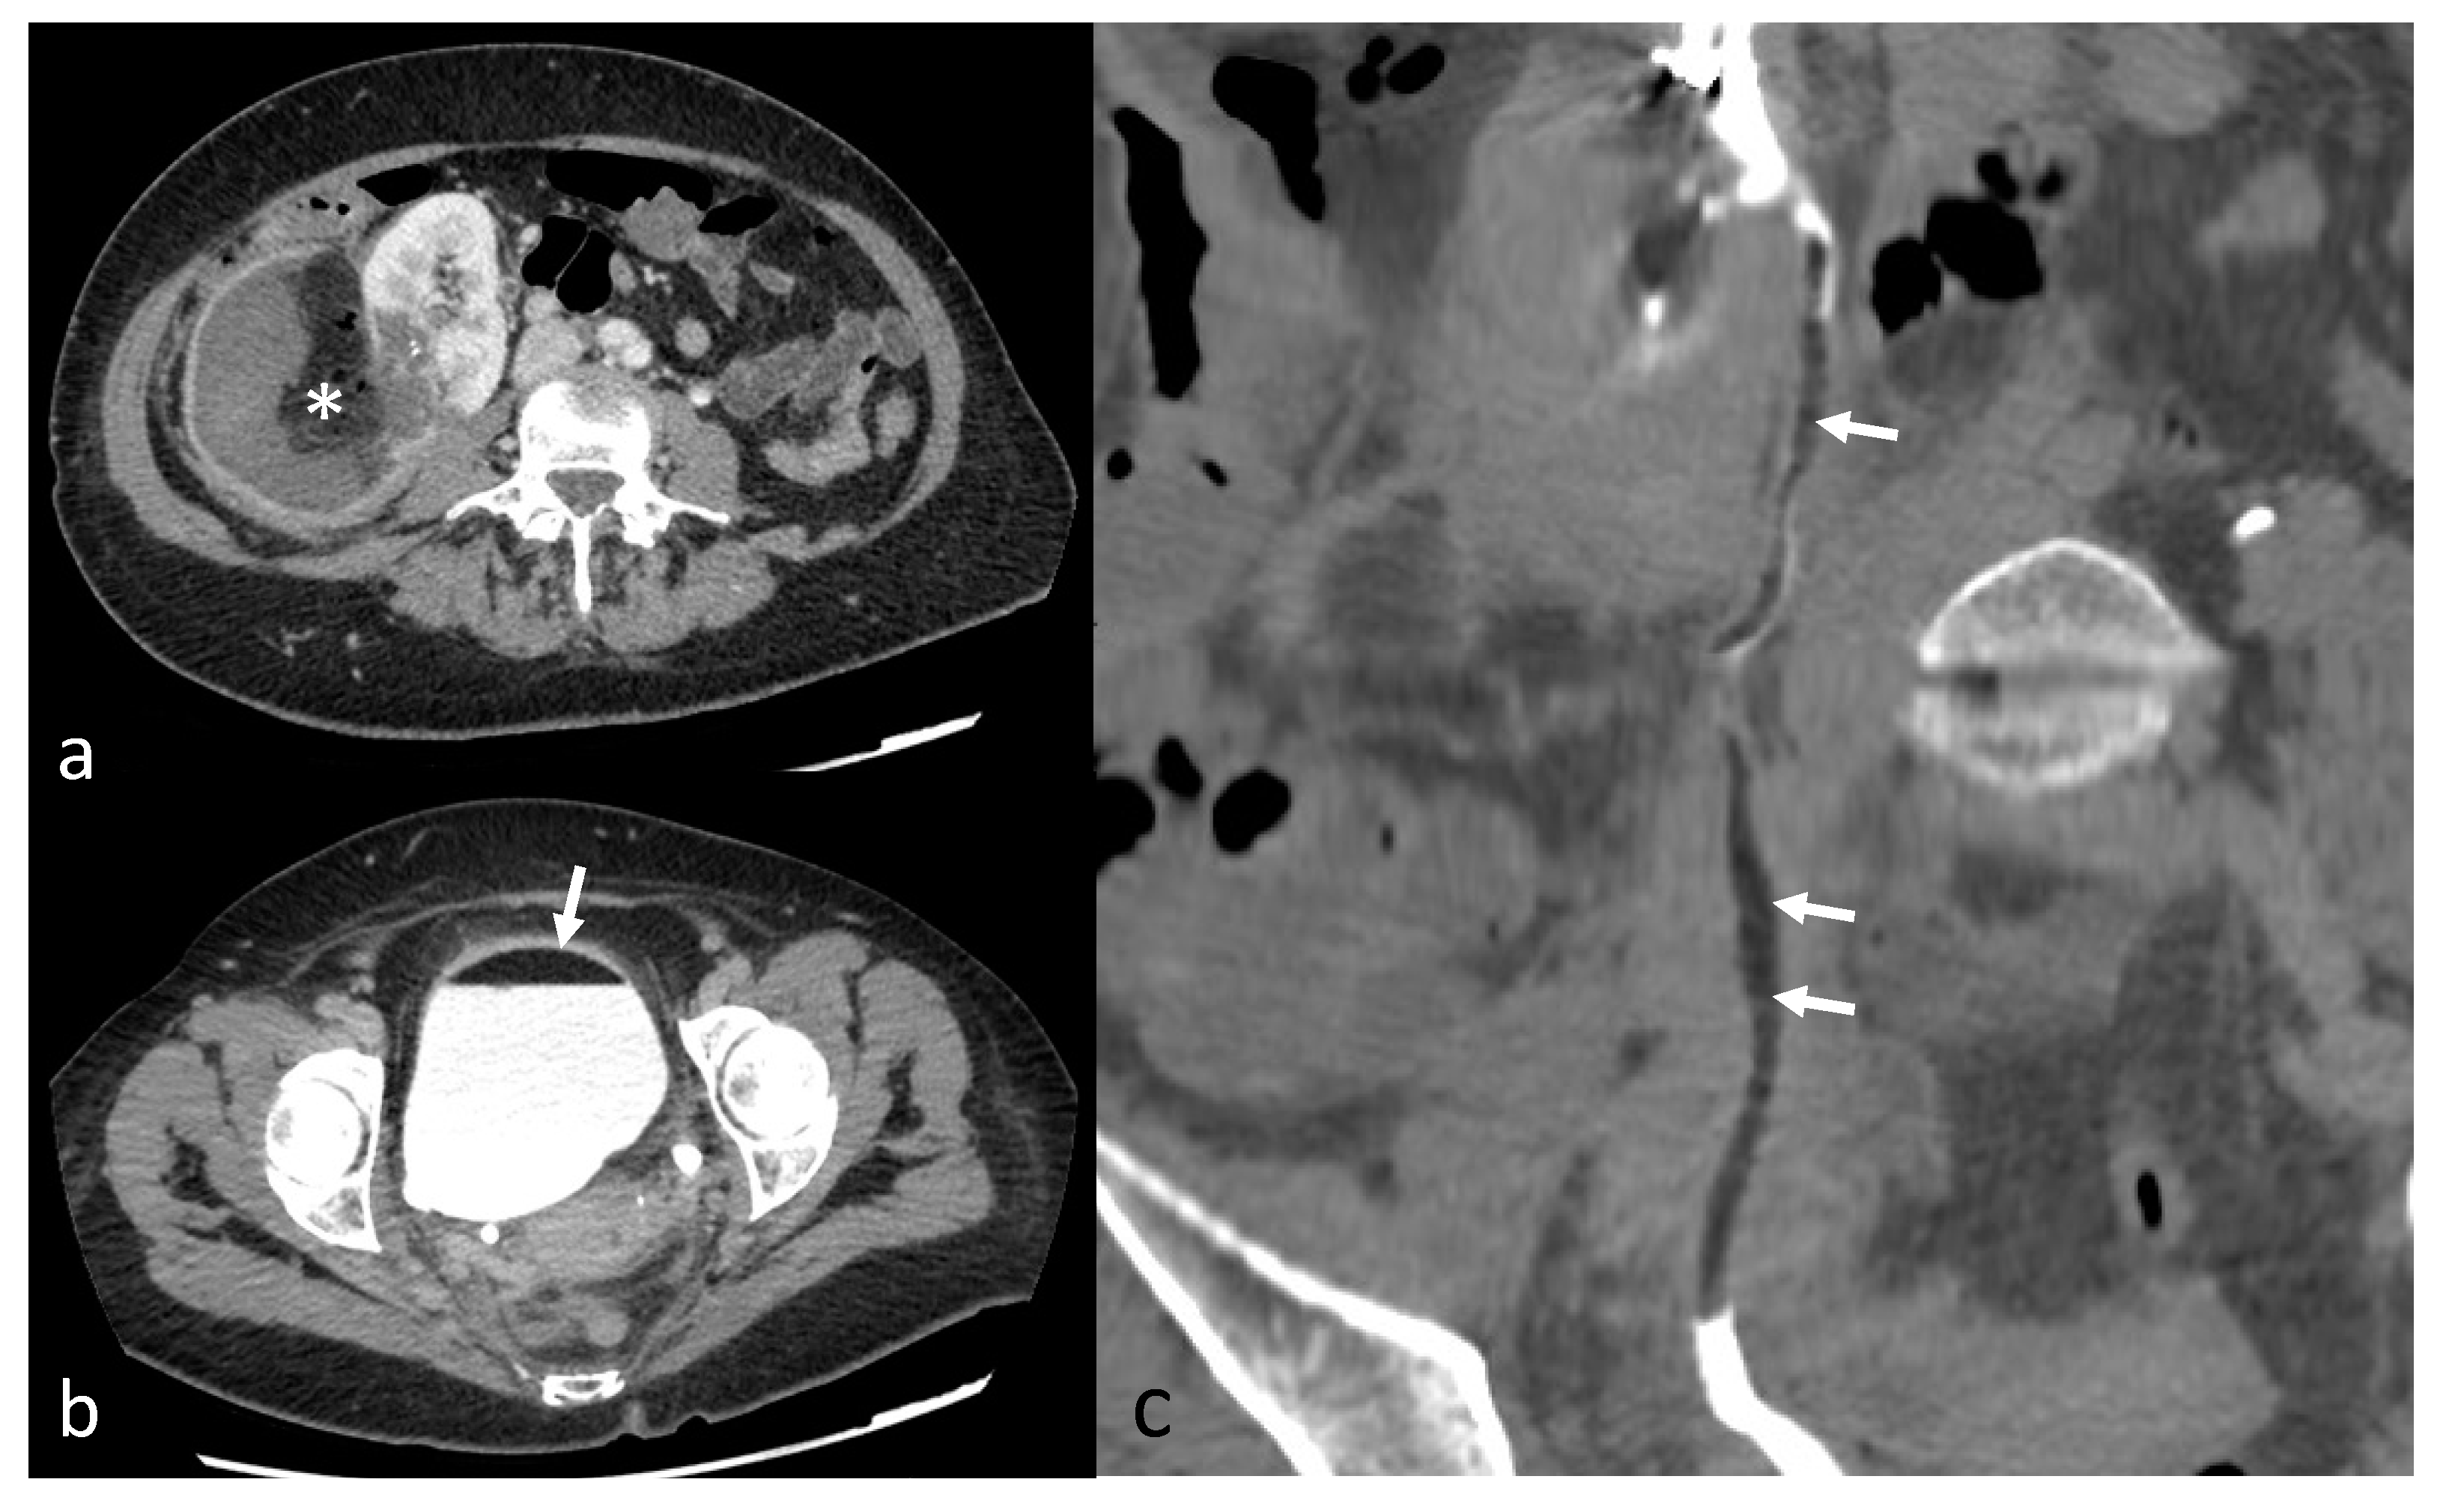

Figure 6.

Postembolization lipuria in a 70-year-old patient with a right AML. (a) Intratumoral necrosis (*) on axial computed tomography with injection and urinary acquisition (b) Fat-supernatant indicating lipuria (white arrow) on axial computed tomography with injection and urinary acquisition (c) Intra-ureteral fat (white arrows) on coronal computed tomography with injection and urinary acquisition.